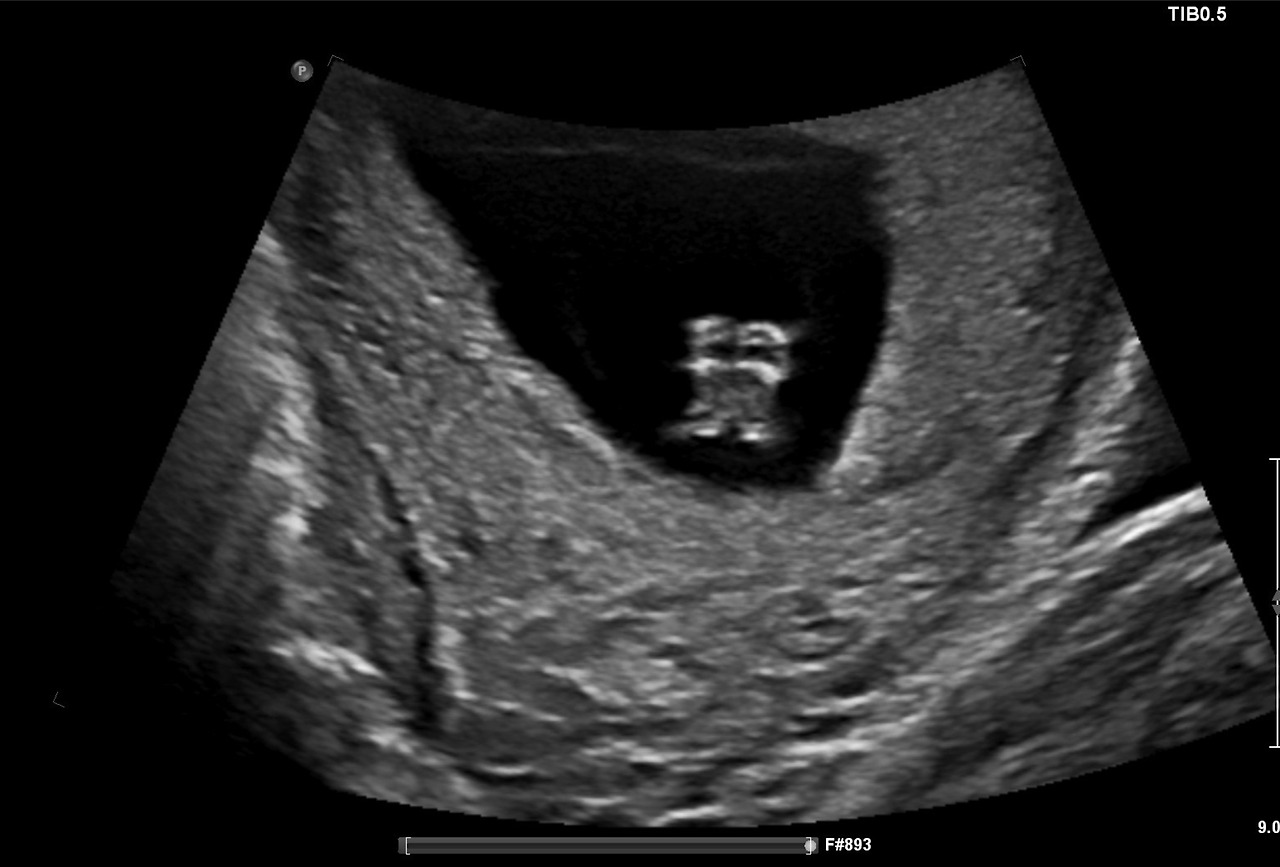

복부 초음파를 통해서는 아이의 목투명대 두께를 측정한다고 하는데, 이는 NT (Nuchal Translucency) scan이라고 불린다. 아이의 목투명대 두께가 3.0mm까지만 정상수치이고, 그 이상으로 넘어갈 경우 다운 증후군이 의심되어 추가 검사를 해야 한다고. 혈액 검사는 몰라도 유독 이 NT scan의 경우는 13주가 넘어갈 경우에는 검사를 할 수 없기 때문에 꼭 11주와 13주 사이에 시기를 맞추어 병원에 가야 한다고 한다.

검사 결과는 역시 며칠 뒤 병원의 웹사이트에서 확인할 수 있었다. 3.0 mm 이하면 정상이라는 목투명대의 두께는 1.7 mm 였다고 하고, 혈액 검사 결과도 아주 양호했다. 이 혈액 검사는 아이 염색체에 이상이 있다 없다 여부를 알려주는 것이 아니라 이상이 있을 확률만을 알 수 있는 검사라고 하는데 타겟이었던 염색체의 trisomy 확률이 아주 낮아서 아주 긍정적인 결과라는 담당 의사의 코멘트를 받을 수 있었다.